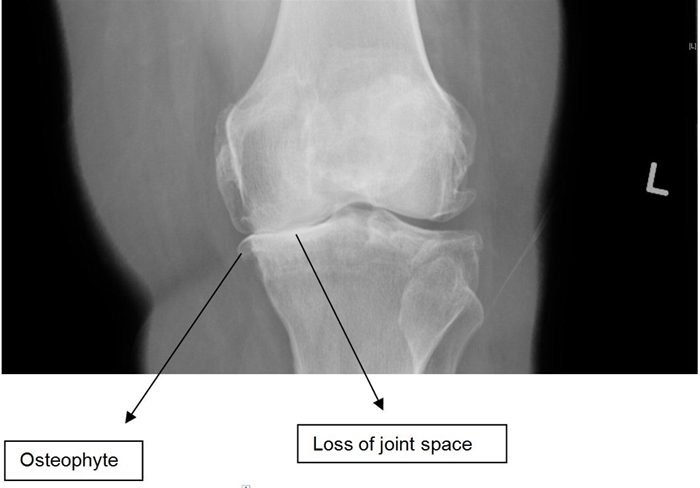

Osteoarthritis

Knee x-ray findings in patients with osteoarthritis include joint space narrowing, subchondral sclerosis, osteophyte formation, and subchondral cysts.